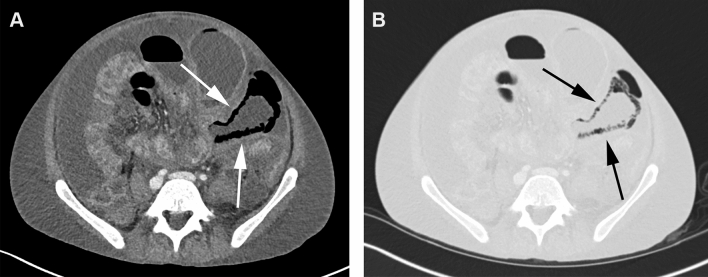

Fig. 3.

CT in the soft tissue (a) and lung window (b) of a 29-year-old male patient with PI in the small bowel (arrows) as well as gas in the mesenteric veins (not shown). The small bowel was distended and showed wall thickening as well. Ascites was present. The AST blood level was 18 IU/L (normal values 7–37 IU/L), the blood lactate level was 3.1 mmol/L (normal values 0.5–2.2 mmol/L). The patient recovered completely